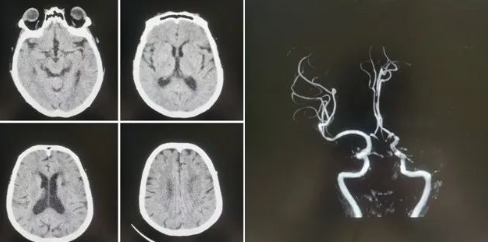

品質(zhì)國(guó)文丨國(guó)文醫(yī)院神經(jīng)介入科成功實(shí)施高難度機(jī)械取栓術(shù)

近日,國(guó)文醫(yī)院神經(jīng)介入科團(tuán)隊(duì)成功實(shí)施了一例高難度的腦血栓機(jī)械取栓術(shù),為一名急性腦梗死患者打通了“生命通道”。這一手術(shù)的成功,不僅標(biāo)志著國(guó)文醫(yī)院在急性缺血性腦卒中救治領(lǐng)域的技術(shù)水平邁上了新臺(tái)階,也為區(qū)域卒中中心建設(shè)增添了新的里程碑。 閱讀量:1354